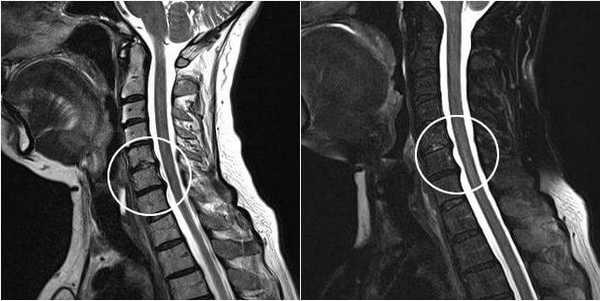

- рентгенография и компьютерная томография: эффективны лишь на поздних стадиях развития заболевания, когда изменения становятся хорошо заметными;

- магнитно-резонансная томография: благодаря высокой степени визуализации, позволяет видеть даже начальные изменения; в настоящее время является основным методом диагностики;